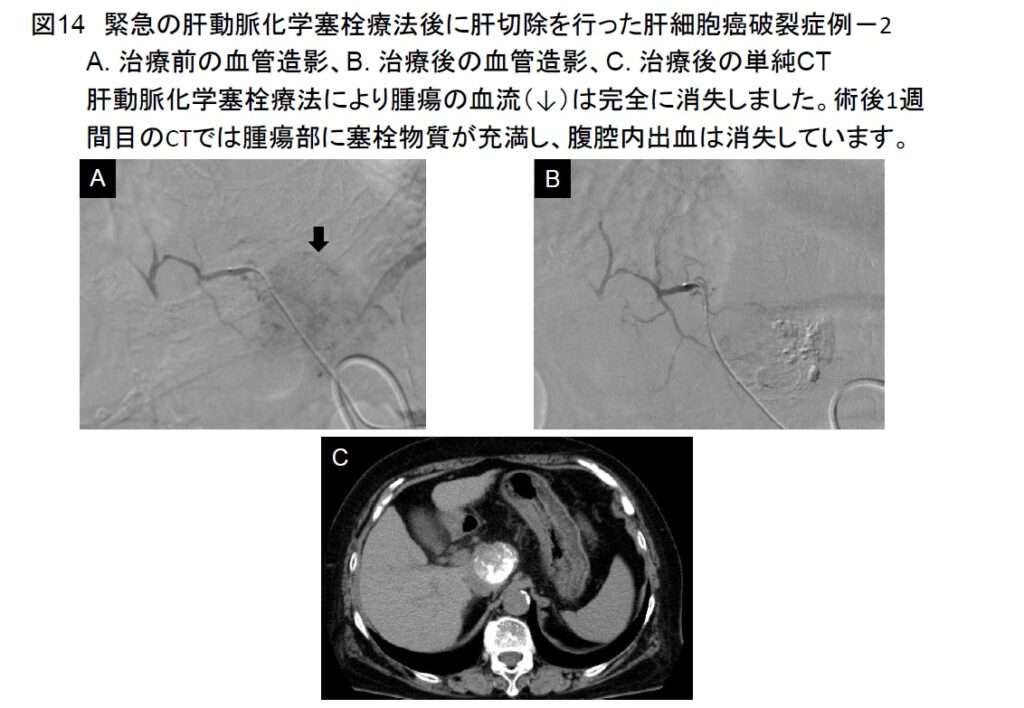

2017年に腹腔鏡肝切除の施設認定を取得し、高難度手術を含めた腹腔鏡肝切除を積極的に行っています(図12)。その他に肝切除例としては、緊急の肝動脈化学塞栓療法後に肝切除を行った症例(図13-16)や門脈塞栓術後に肝切除を行った大型肝細胞癌症例を経験しました(図17-19)。いずれも経過は極めて良好です。肝切除の適応決定時には、3次元画像解析シナプスVINCENTTMによる肝体積評価やアシアロSPECT-CT 融合画像による機能的肝体積評価を行い、より安全な手術を目指しています(図20)。